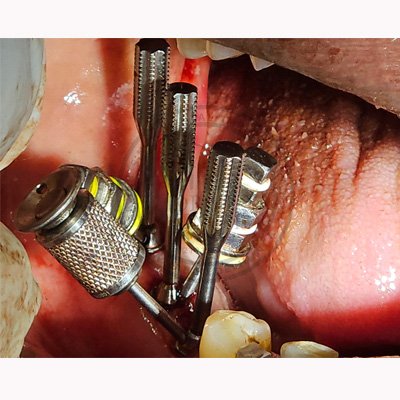

Case – 11 Baleram